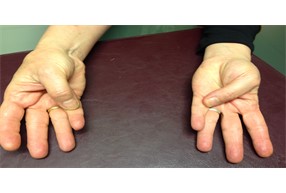

- Σε προχωρημένες καταστάσεις, μπορεί να παρατηρηθεί δημιουργία οστεόφυτων στη βάση του αντίχειρα και υπερέκταση της ΜΚΦ άρθρωσης, δίνοντας την χαρακτηριστική Ζ παραμόρφωση.

Εικόνα 2: Z παραμόρφωση